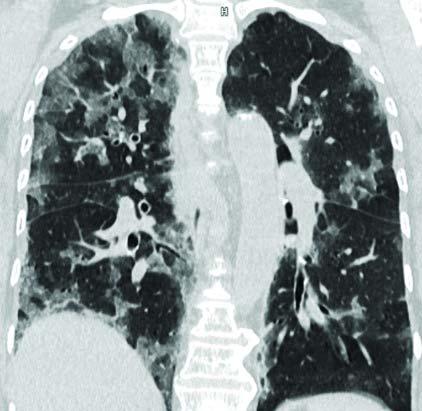

(Image 03) CORONALIMAGE SHOWING THE LESION DISTRIBUTION (Image 04) PULMO 3D Image SHOWING LESIONS (WHITE) SURROUNDING THE BLOOD VESSELS(RED) (Image 05) PULMO 3D IMAGE OFBRONCHIALTREE (MULTICOLOR) AND THE LESIONS (WHITE) RELATIONSHIP

(All the belowimages are acquired on Siemens Healthineers CT,SOMATOM go.Top and processed on Siemens Advanced modality Workstation syngo.via)